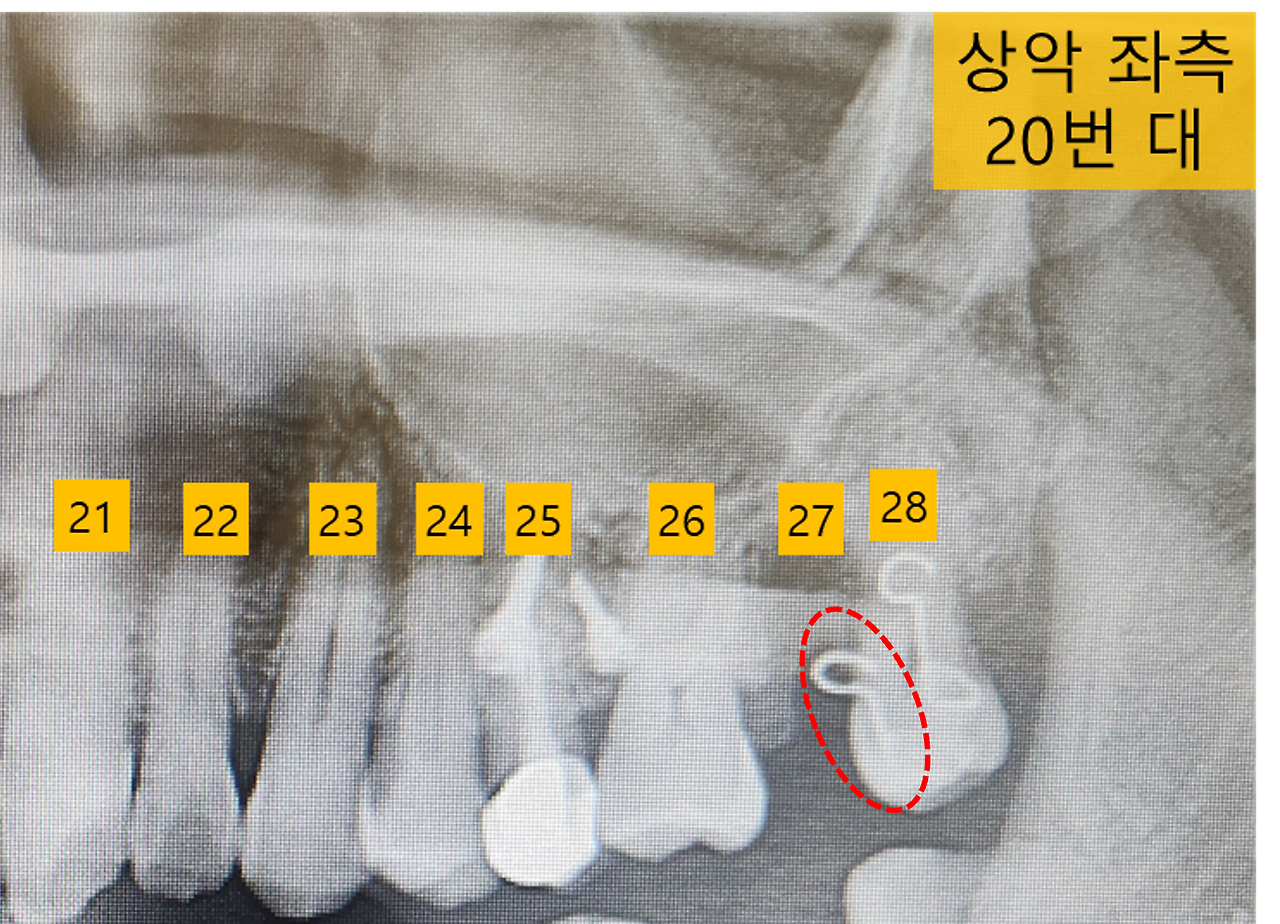

파노라마 사진_교정 떨어짐.png [떨어진 교정 장치]

교정 담당의사분이 와서 떨어진 교정 부위를 확인하고 간 후, 간호사분이 붙어있던 접착제를 제거하기 시작했습니다. 그리고는 접착제가 잘 붙을 수 있도록 치아에 다시 엣칭작업을 진행했습니다. 잠시 후 간호사분이 혹시 떨어진 교정 장치를 가지고 있냐고 물어보길래, 호주머니에 넣어두었던 것을 꺼내서 건네주었지요. 간호사분이 무척 반겨하며 다행이라고 합니다.

이유인즉슨 오른쪽 교정 장치는 범용적 형태라 분실해도 큰 문제가 없지만, 왼쪽 교정용 장치는 제 구강 구조에 맞춰 제작된 맞춤형이라, 만약 분실하였거나 버렸다면 다시 제작을 해야 한다고 합니다. 부서진 것 같아 버릴까 고민했었는데 가져오길 정말 잘했네요. 혹시 나중에 교정하시는 분이 계시다면 떨어진 교정 장치는 꼭 챙기시길 바랍니다. ㅎㅎ.